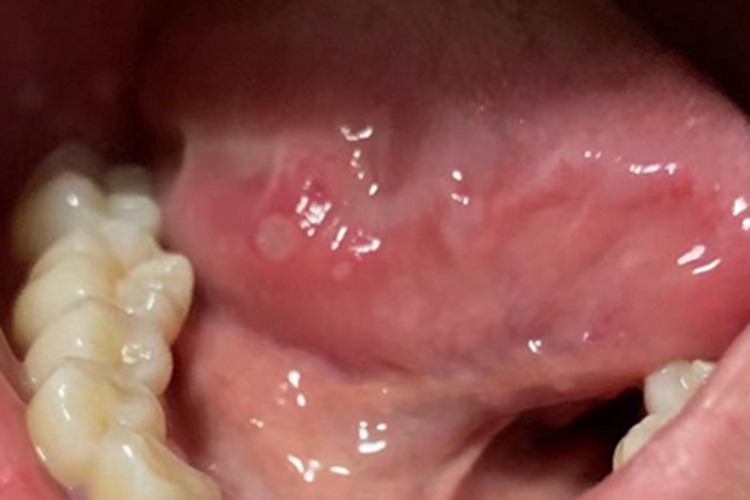

轻型阿弗他溃疡患者舌侧面可出现红肿,红肿的黏膜上可见大小不一的白点,呈圆形,伴有明显的灼痛感,一般并无明显的全身症状。